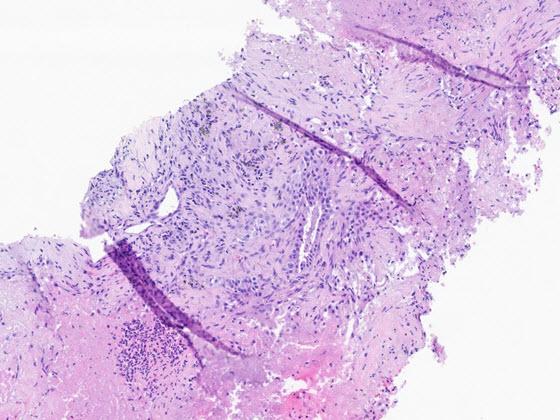

High quality slides are a prerequisite for a first-rate digital workflow. Artifacts generated in the slide creation and scanning process can not only affect interpretation but can prevent image analysis and AI tools from rendering the correct results. SlideQC BF automatically detects and annotates artifacts present on images, increasing the accuracy and quality of the analysis results while maximizing scanned tissue. Artifacts may include pen marks, out of focus areas, tissue folds, debris, or bubbles.